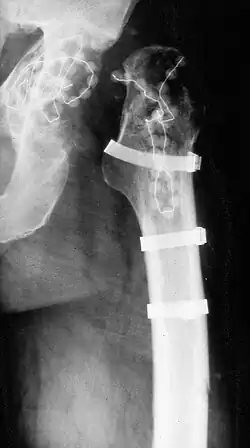

Girdlestone-Operation

Girdlestone-Hüfte nach Ausbau einer infizierten Endoprothese

Die Girdlestone-Operation ist ein operativer Eingriff in der Orthopädie und Unfallchirurgie, bei dem der Femurkopf reseziert wird. Eine solche Girdlestone-Hüfte entsteht auch durch den (zunächst) ersatzlosen Ausbau einer infizierten Endoprothese.